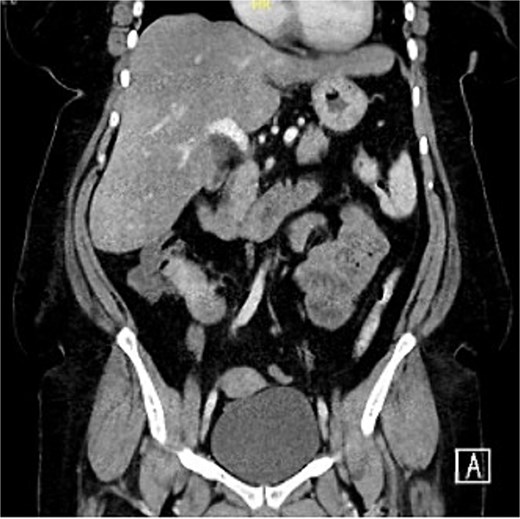

A 54-year-old female presented with intermittent right lower quadrant abdominal pain, distension, and constipation persisting for 1 year, with symptom progression in the last 2 months. There are no other gastrointestinal nor constitutional symptoms. The patient has no previous medical or surgical history. On examination, the patient was alert, oriented, and hemodynamically stable. The abdomen was mildly distended, however, soft, with right lower quadrant mild tenderness and localized fullness. A digital rectal examination revealed an empty rectum with no visible or palpable pathology. Laboratory workup was insignificant. Erect and supine abdominal X-rays, performed to evaluate possible obstruction, showed no abnormalities. Computed tomography (CT) scan (Fig. 1) showed a hyper-enhancing spiculated ill-defined lesion at the right lower mesentery measuring about 2.9 × 2.2 × 2.4 cm, with no internal calcification or macroscopic component associated with thickening and tethering of the adjacent bowel loops named terminal ileum and cecum, causing tethering and stranding of the mesentery. No mechanical bowel obstruction.

Hyper-enhancing spiculated ill-defined lesion at the right lower mesentery measured about 2.9 × 2.2 × 2.4 cm, with no internal calcification or macroscopic component associated with thickening and tethering of the adjacent bowel loops.